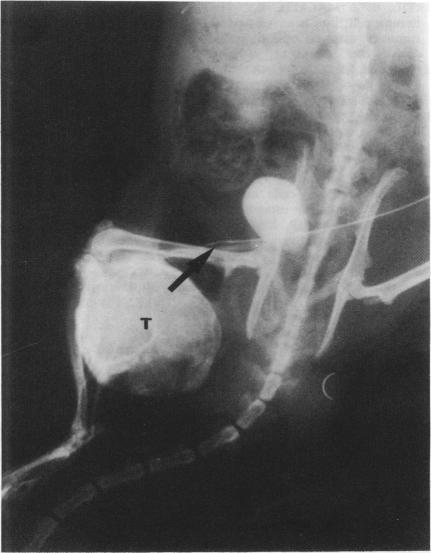

Systemically administered radiolabelled anti-tumour antibody is ineffective in treating the majority of patients with liver metastasis from colorectal carcinoma. We have assessed whether agents which increase capillary permeability can increase tumour uptake of antibody isotope conjugate. We developed a xenograft model of colorectal carcinoma using an antibody directed against carcinoembryonic antigen (CEA). Tumours were grown subcutaneously in the hind limbs of athymic rats to derive their circulation from the femoral artery. Cannulae were placed in the common iliac artery and iliolumbar vein. Antibody was delivered systemically, regionally and regionally with histamine, leukotriene C4 and interleukin-2. Regionally administered anti-CEA antibody resulted in a significantly greater (P = 0.004) tumour to normal tissue ratio (1.66, s.d. = 0.68) compared to systematically administered antibody (1.25, s.d. = 0.73). The addition of vasoactive drugs produced an approximately 3-fold increase with an increase to a mean tumour:liver ratio of 3.24 (s.d. = 1.39) for histamine (P less than 0.001 compared to systemic delivery), 3.21 (s.d. = 1.13, P less than 0.001) for leukotriene C4 and 3.80 (s.d. = 1.53, P less than 0.001) for interleukin-2. The addition of histamine significantly (P = 0.004) increased the mean tumour to liver ratio (1.73, s.d. = 0.44) of non-specific antibody uptake compared with either systemic (1.12, s.d. = 0.24) or regional delivery (1.25, s.d. = 0.54) of non-specific antibody alone. Increasing tumour capillary permeability can produce a significant clinically useful increase in tumour uptake of antibody-isotope conjugate.